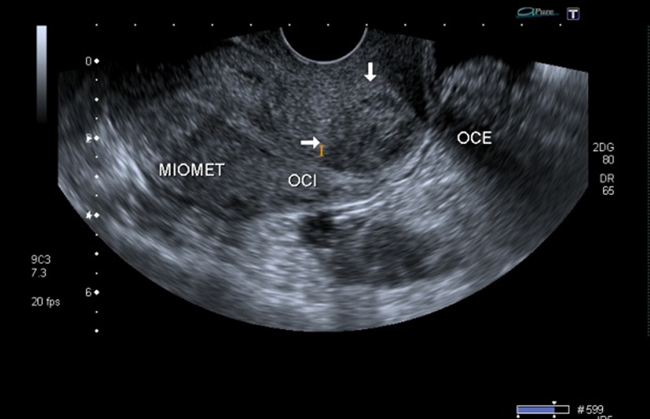

A la paciente se le realizó una prueba en sangre para cuantificar la fracción beta de la gonadotrofina coriónica humana (Abbott Laboratories. Architect.B-hCG Total), que se reportó en 31.819 mUI/ml. También se le tomó una ecografía endovaginal (Toshiba-Xario XG) que mostró la presencia de útero con medidas de 72 × 52 × 54 mm con un cuello de 35 mm con orificio interno cerrado. El endometrio midió 18 mm, sin evidencia de saco gestacional intrauterino y en la región ístmica y cervical, por debajo de las arterias uterinas, se encontró un saco gestacional de 30 mm con presencia de embrión único de 20,6 mm sin presencia de actividad cardiaca fetal (figuras 1 a 4).